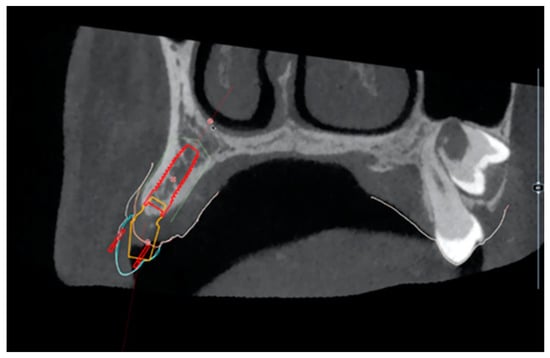

2.3. Surgical and Prosthetic Workflow